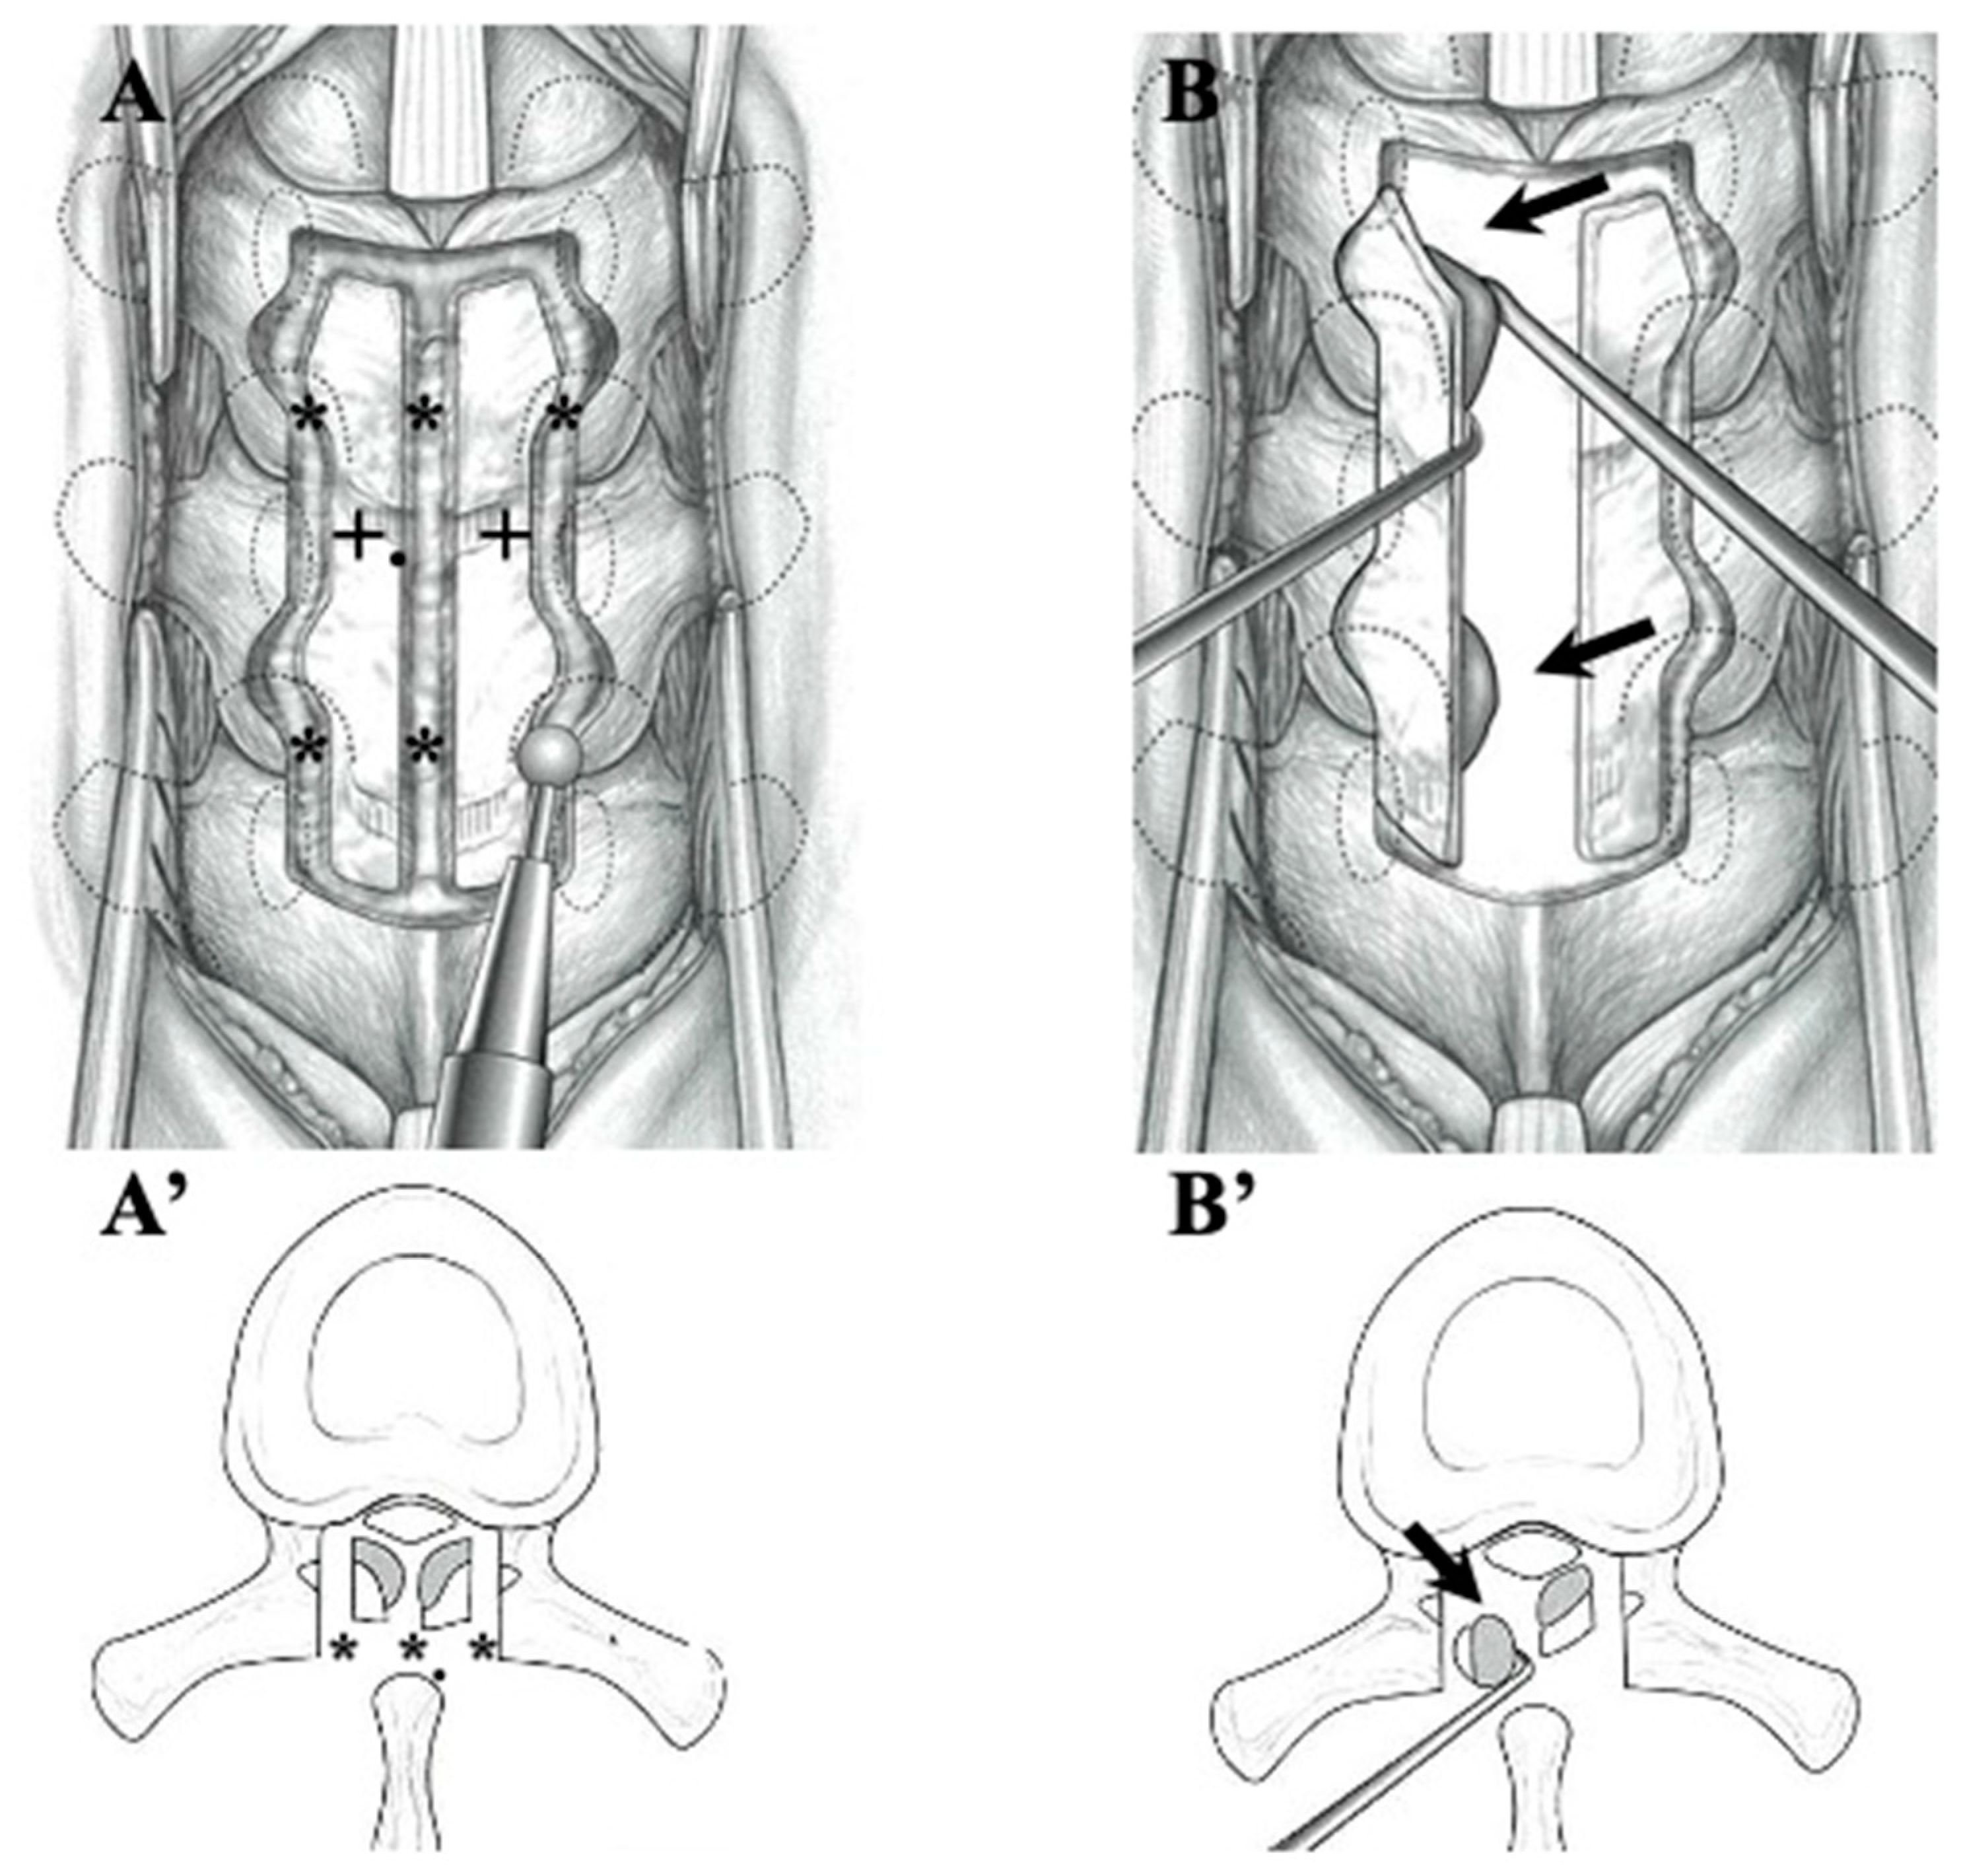

OLF: In the cases of OLF, instances where the ligamentum flavum adhered to the dura mater were not uncommon, and ossification extending to the intervertebral foramen was also frequently observed. Therefore, we adopted laminectomy following the approach outlined in Figure 2. In cases where ossification did not extend to the intervertebral foramen nor adhered to the dura mater, we attempted en-block laminoplasty, considering the need to reconstruct posterior supporting tissue for long-term outcomes. A gutter with a similar width to the spinal canal was created, and the OLF was drilled out from the laminae. In cases where OLF was severely adherent to the dura mater, part of the OLF was intentionally left behind (Figure 2) [50,51]. For cases with instability, single-stage laminectomy with PLF was performed [49].

Figure 2.

Illustrations demonstrating laminectomy for OLF in the thoracic spine. After thinning the lamina (black cross), cranial, caudal, lateral, and midline garters were made by drilling (black asterisks) (A,A’). The OLF was carefully dissected from the dura matter and removed (black arrows) (B,B’).

OLF: In OLF, as an operative procedure, laminectomy was generally indicated. But we think that to prevent post-operative kyphosis, we should try to perform laminoplasty for the possible case where ossification does not extend to the intervertebral foramen nor adhere to the dura mater, as illustrated in Figure 5B,B’. Since most cases of OLF exhibit adhesion to and penetration into the dura mater, caution is required during OLF removal, as illustrated in Figure 2. In cases with adhesion to the dura mater, it may be necessary to carefully preserve the OLF or suture defects in the dura mater after the dissection of the OLF (Figure 2) [49,51].